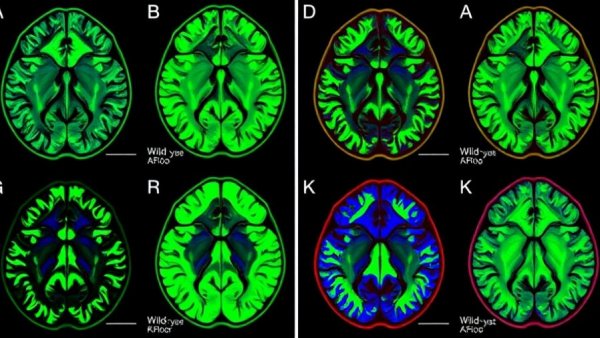

Fluorescent brain slices showing Shank3-related autism treatment pathway data.

Research shows that individuals with ASD often present variants in the Shank3 gene, which is pivotal for neuronal communication. The implications of mutations or deletions in this gene are profound, leading to white matter abnormalities that have been consistently observed in affected individuals. Notably, white matter—integral for signal transmission—relies heavily on proper myelination performed by oligodendrocytes. Thus, any disruption in the growth and function of these cells can lead to significant communication hurdles in the brain.

The Exciting Findings from Ulm University

A recent study led by researchers at Ulm University and the German Center for Neurodegenerative Diseases has unveiled that the absence of Shank3 disrupts oligodendrocyte maturation due to hyperactivation of the Erk signaling pathway. By pharmacologically inhibiting this pathway, the researchers noted an improvement in oligodendrocyte maturation, and, crucially, this intervention partially alleviated behaviors associated with autism in their Shank3-deficient mouse models. This suggests that targeting the Erk pathway could be a promising therapeutic strategy for those affected by Shank3-related ASD.

Diving Deeper: The Erk Pathway's Role

The study found that Erk signaling is crucial in regulating oligodendrocyte maturation. Its overactivity led to a detrimental production of myelin—indicative of hypomyelination—in the absence of Shank3. This connection underscores how genetic factors can shape developmental neurobiology, affecting everything from cognitive function to social interactions. As families look to resources in places like Muskegon, Michigan, for personalized autism treatments, the possibility of pharmacological solutions derived from this research paints a hopeful picture for treatment.